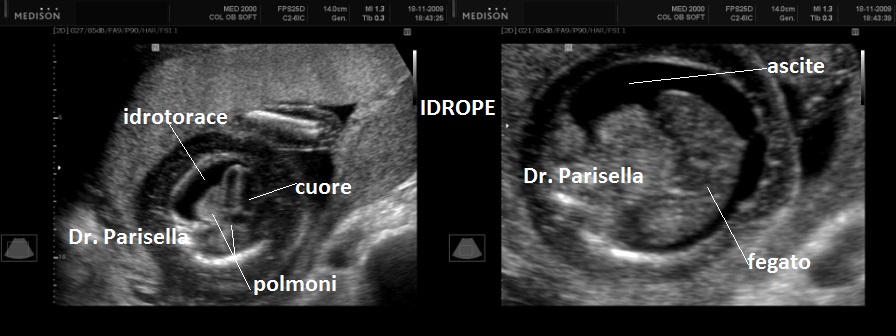

E' caratterizzata da grave ritardo di crescita intrauterino, grave microcefalia, lissencefalia tipo 3  e dismorfismi facciali consistenti in ipertelorismo, micrognazia, grave esoftalmo, anomalie auricolari, naso piatto; una caratteristica è l'edema spiccato che interessa cranio, gomiti, ginocchia, mani e piedi (si ha quasi l'impressione che le dita siano assenti); vi è inoltre assenza dei movimenti attivi fetali (SAF) e possono esservi contratture articolari (artrogriposi) caratterizzate da arti superiori ed inferiori in flessione.

I segni ecografici sono numerosi :

4. edema spiccato,

9. idrope,